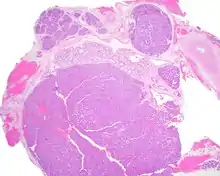

Canalicular adenoma is a type of growth that occurs in human salivary glands. It is a benign growth which occurs in the epithelial cells, and is typically arranged in columns of cells that form interconnecting cords. Canalicular adenoma is a very rare benign neoplasm; it constitutes about 1% of all salivary gland tumors and about 4% of all benign salivary gland tumors.[1][2]

Canalicular adenoma is most common in patients age 70 to 80, with females affected about four times as often as males. Most growths present in the upper lip; some also occur in the a few present in palate or buccal (cheek) tissue as a slowly enlarging mass.[3] The growths will often arise in multiple places at the same time or develop multiple nodes, despite not being clinically invasive or malignant.[1][4]

Canalicular adenoma growths are usually small at the time they are noticed, with an average size of about 1.6 cm.[1] Their histologic appearance is very distinct, with a channel-like pattern between cords and ribbons; the pattern has been described as resembling a "string of pearls."

The growths often contain are often small bight squamous balls, or morules. They also tyipcally contain a well-developed supporting tissue - a fibrous stroma - which is rich in hyaluronic acid and chondroitin sulphate.[1] In a few cases, the growths may contain small calcium deposits or microliths. Although it is seldom necessary, a pathologist can confirm the existence of canalicular adenoma through immunohistochemistry studies, with the cells reacting with pancytokeratin, S100 protein and SOX10, with a delicate GFAP reaction around the periphery.[5][1][6][7] Although it is a benign tumor, a positive diagnosis of canalicular adenoma may be necessary to exclude the existence of other medical conditions such as a basal cell adenoma, pleomorphic adenoma, adenoid cystic carcinoma, and polymorphous adenocarcinoma.